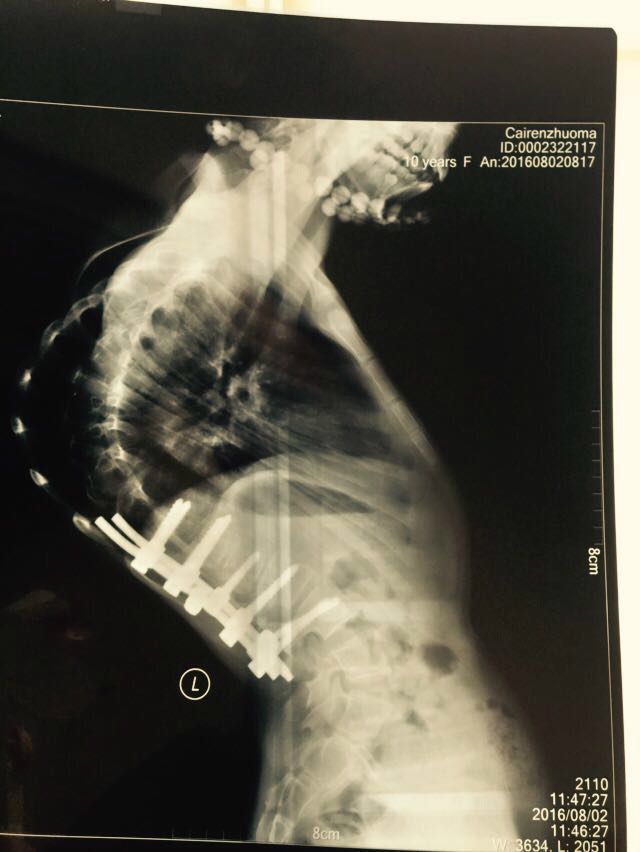

小卓玛是玉树地震孤儿,藏族。11岁的她身高和6-7岁的小朋友差不多。因从小失去父母,她性格内向,不爱说话,平时很少与人交流。2013年4月,志愿者在玉树探访时发现患有严重脊柱侧弯的小卓玛,医生说如果她不能在10岁前做手术,将危及生命。

小卓玛的矫正手术需分两次做,否则很难长高。第一次没有公募,千方百计地通过志愿者捐助把卓玛接到北京,在儿童医院完成了首次手术,康复后送回青海,总成本约15万。因西宁没有医院能更换矫形护具,随着卓玛的生长,每年暑假还要接卓玛到内地大医院更换护具。三年来,在大家的帮助下,卓玛健康成长,普通话也成为班里最好的。

她从小就知道自己跟别的小朋友不同,后背上那个外翻的脊柱让她不能随意跑跳,但至少还能正常行走。小小年纪的她,完全不知道后面有多少风险在等着她,特别是瘫痪意味着什么,无亲无故的孩子若一旦卧床不起,谁能承担照料她的责任。